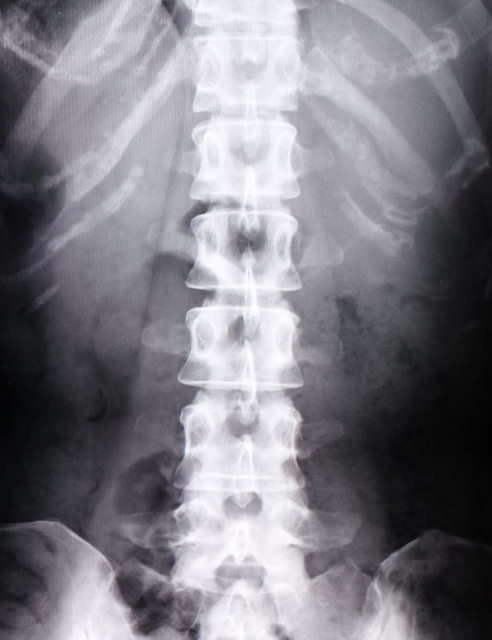

仙腸関節とは骨盤にある仙骨と腸骨を繋ぐ関節です。

関節と言っても肩や股関節と違いほとんど動きがないもしくは全く動きのない関節です。

仙腸関節にはたくさんの靭帯で補強されるためほとんど動かないですが、数ミリの動きがあると言われています。

関節の機能異常な為、レントゲン撮影やMRI検査をしても異常は見つけられません。